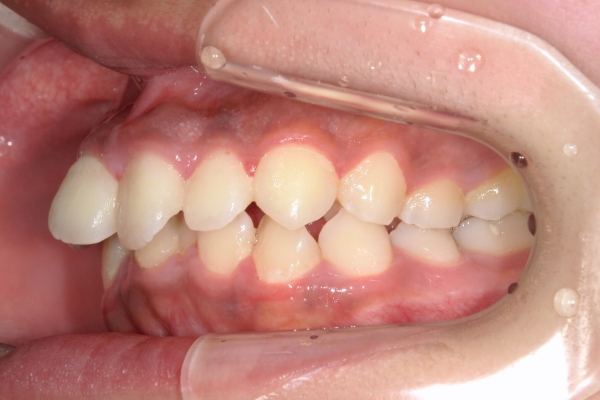

BEFORE

治療前

AFTER

治療後

上顎前歯が1 cm近く前方に出ており、叢生を改善しつつ前歯を大きく引っ込めるために上下顎小臼歯の抜歯が必要と診断しました。治療では奥歯の噛み合わせのズレも整え、治療後は前歯でも奥歯でも食べ物が噛みやすくなったと、患者さまに非常に満足していただけました。